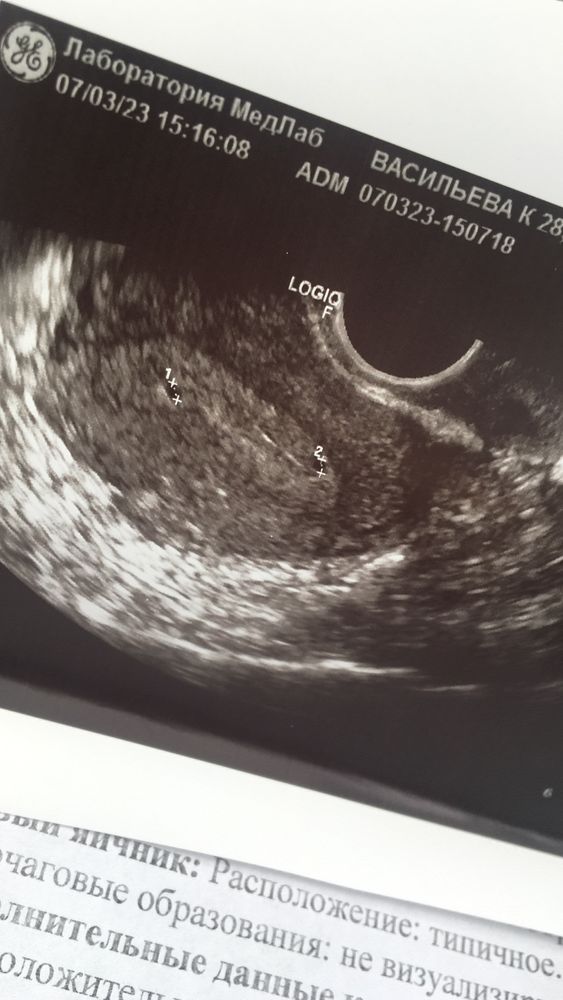

Катрин, история очень странная , я и одного то не ждала 🙈 а тут два сразу спасибо ☺️

Девочки, 6 неделя беременности можно красить брови хной и делать гель лак? Первое узи